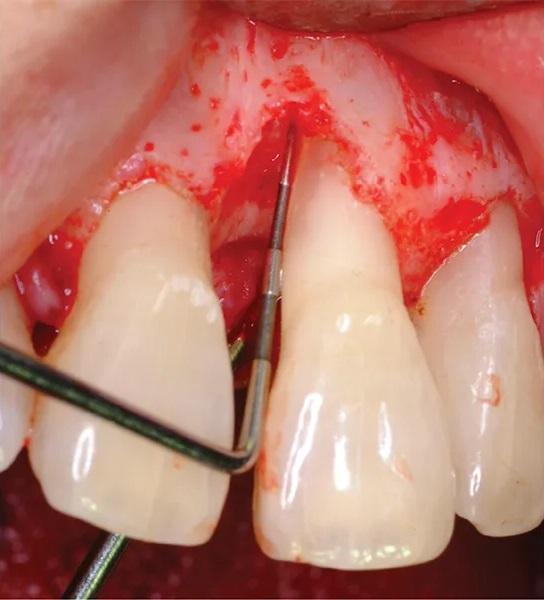

65-летняя некурящая пациентка с пародонтитом обратилась с костным дефектом на мезиальной поверхности верхнего левого центрального резца (зуб № 2.1) (Фото 1 и Фото 2). Зарегистрированный индекс подвижности (по Грейсу и Смейлсу) составил 2 степень, т.е. движение в вестибуло-лингвальном направлении на 1–2 мм. Во время процедуры пластики был отслоен слизисто-надкостничный лоскут, обнажен глубокий пародонтальный дефект (Фото 3 и Фото 4). Аутогенная кость была взята из ветви нижней челюсти и смешана в соотношении 1:2 с ДМБК (покрытый ОКФ, 100% губчатая кость) (Ti-oss, Chiyewon Co. Ltd.; распространяется как creos xenoform, Nobel Biocare). Полученный материал был смешан с высококонцентрированными тромбоцитами, полученными путем дополнительного центрифугирования БоТП (упоминается как концентраты тромбоцитов в протоколе, адаптированном автором), к которым были добавлены тромбин и кальций для образования коагулированной массы (Фото 5), использованной для заполнения дефекта (Фото 6). Показано, что тромбин и кальций in vitro и in vivo активируют тромбоциты для высвобождения факторов роста, тем самым стимулируя остеобласты, усиливая ангиогенез и способствуя миграции клеток.

Фото 4. Интраоперационное клиническое изображение с зондом, показывающим глубину дефекта.